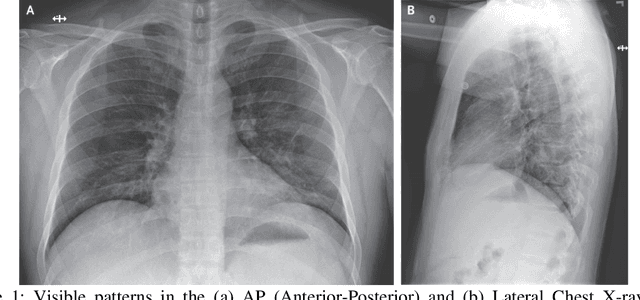

Abstract:The recent outbreak of COVID-19 has halted the whole world, bringing a devastating effect on public health, global economy, and educational systems. As the vaccine of the virus is still not available, the most effective way to combat the virus is testing and social distancing. Among all other detection techniques, the Chest X-ray (CXR) based method can be a good solution for its simplicity, rapidity, cost, efficiency, and accessibility. In this paper, we propose CovMUNET, which is a multiple loss deep neural network approach to detect COVID-19 cases from CXR images. Extensive experiments are performed to ensure the robustness of the proposed algorithm and the performance is evaluated in terms of precision, recall, accuracy, and F1-score. The proposed method outperforms the state-of-the-art approaches with an accuracy of 96.97% for 3-class classification (COVID-19 vs normal vs pneumonia) and 99.41% for 2-class classification (COVID vs non-COVID). The proposed neural architecture also successfully detects the abnormality in CXR images.